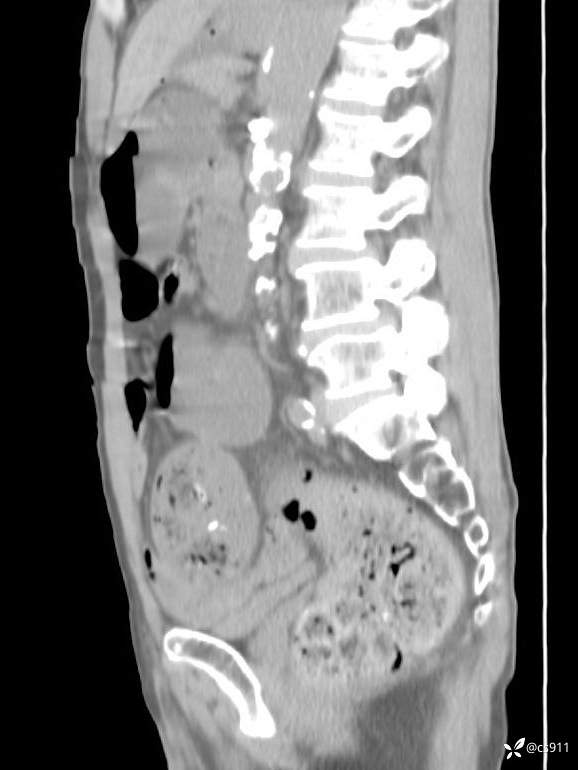

急腹症之急诊CT,原因?答案公布

男,77岁,腹痛、腹胀伴恶心呕吐1天。呕吐胃内容物,非喷射性呕吐,有咖啡色样胃内容物,诉有胃穿孔病史。查体:全腹平,下腹部压痛,全腹无反跳痛,叩诊呈浊音,移动性浊音阴性,肠鸣音减弱,1-2次/分。肛检:直肠未扪及明显肿物,可触及大量粪块。

T 36.6℃ P 80次/分 R 26次/分 BP 100/60mmHg

白细胞(WBC) H 14.55 10e9/L 4-10

中性粒细胞百分率(NEUT%) H 85.7 % 40-75

血淀粉酶(AMY) HH 1859 U/L 35-135

癌胚抗原(CEA) H 27.44 ng/ml 0-5

呕吐物 潜血试验 * 阳性 阴性

患者轮椅入室检查神志清楚, 能配合摆位和呼吸